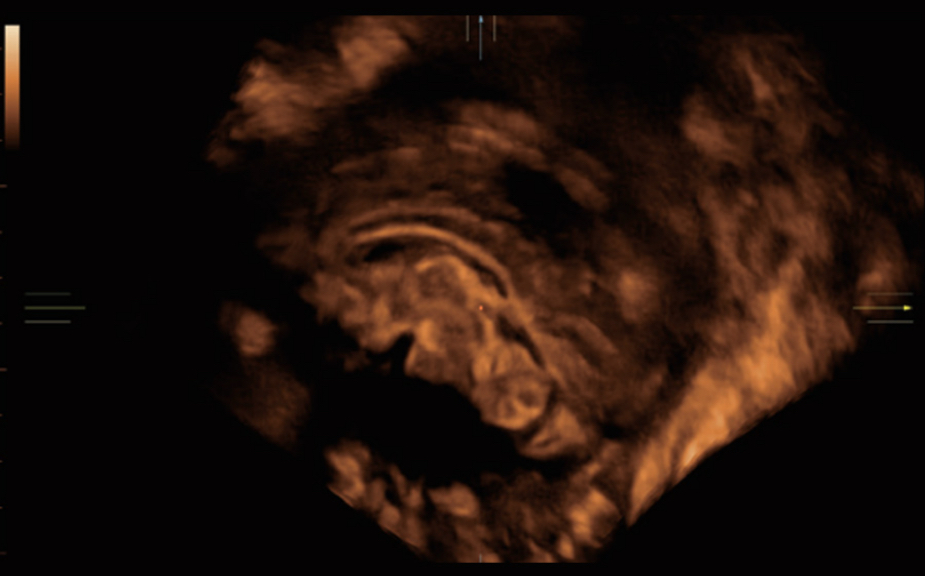

Gambar Klinis